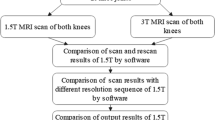

A senior-level radiologist, who was blinded to the volunteers’ clinical information, evaluated the extent of cartilage degeneration and hydrarthrosis. Cartilage score criteria was obtained using the Whole-Organ Magnetic Resonance Imaging Score (WORMS) and ranged from 0 to 2. Knee cartilage was automatically segmented into 21 subregions [14] using post-processing prototype software (MR Chondral Health, version 2.1, Siemens Healthcare, Erlangen, Germany). This software automatically divides the knee cartilage into three main parts—femoral, patellar, and tibial cartilage—consisting of 21 cartilage subregions. The T2* maps were automatically registered to 3D DESS images by prototype software. The cartilage volume and mean T2* relaxation time for each subregion were also derived automatically by the software. The corrected slice was the slice that needs to be manually adjusted after automatic segmentation (Fig. 1). The T2* relaxation time of cartilage in the knee was measured by the same doctor twice a week apart to test consistency among observers. The automatic segmentations were manually corrected to increase overall segmentation accuracy. The Dice coefficient was used to quantify the amount of change performed on the automatic segmentation [5, 11]. The Dice correlation between automatic segmentation A (fA(x)) and manual correction based on the automatic segmentation B (fB(x)) was defined as in Equation: Dice (fA(x),fB(x)) = 2·fA(x)·fB(x)/(fA(x) + fB(x)). Levels of hydrarthrosis and cartilage scores (by WORMS) were determined to analyze their influence on the segmentation accuracy of each cartilage subregion.